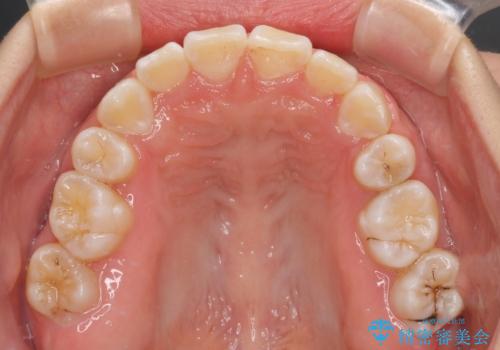

重度叢生と埋もれた奥歯 8本を抜歯したワイヤー矯正

奥歯の移動、特に下顎大臼歯の移動は時間がかかることが多く、3年以上の治療期間を想定していましたが、想像以上に動きがよく、2年強で終えることができました。

親知らずの抜歯により埋もれた奥歯周辺の歯肉が切除され、矯正装置が装着できるようになりました。